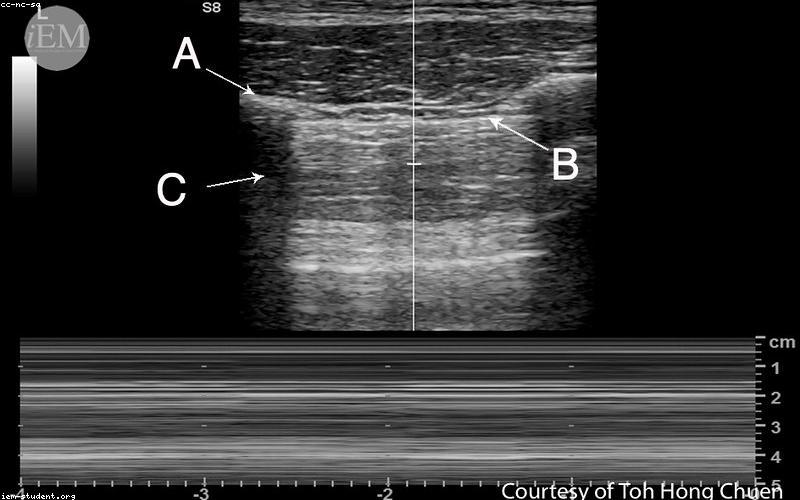

Mỗi lần siêu âm định kỳ, Bác sĩ Nga đều kiểm tra kỹ lưỡng từng chỉ số phát triển của thai nhi, tư vấn thực đơn dinh dưỡng theo từng giai đoạn và đặc biệt là hỗ trợ giải tỏa những cơn lo âu bất chợt của chị Minh Anh. Những dòng tin nhắn tư vấn lúc nửa đêm hay những lời động viên kịp thời đã giúp chị vượt qua giai đoạn nhạy cảm nhất.